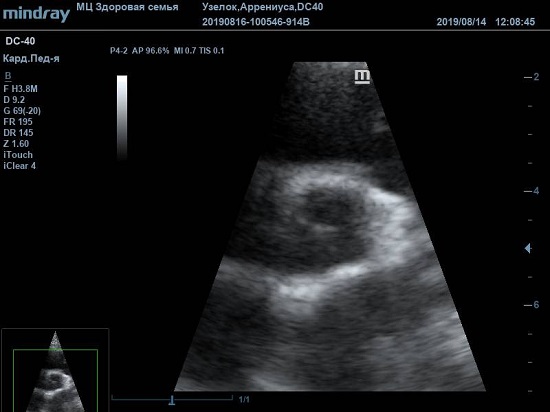

Существует вариантная анатомия, например, наросты Ламбла или гипертрофия узелков Аррениуса на полулуниях аортального клапана. Узелки и наросты увеличивают занимаемый объем полулуния, при этом нарушая конгруэнтность поверхности створок или полулуний клапана. В итоге закрытие осуществляется не полностью, и возникает легкая недостаточность. Именно такие случаи часто обнаруживаются у детей и не требуют специального лечения или пристального наблюдения.

Найти их очень просто, достаточно сечений LAXLV (длинная ось) и SAXBASE (короткая ось). Специфические крупные шаровидные структуры – узелки Аррениуса - на кончиках полулуний клапана обнаружил ультразвуковой прибор Mindray DC-40. В цветовом допплере без труда определяется аортальная регургитация легкой степени. Оценить её можно в CFM по соотношению JW/LVOT.

Приборы среднего класса прекрасно справляются с этой задачей. Чтобы использовать возможности прибора на максимум необходимо уменьшить поле обзора (Front of view - FOV), тогда увеличится частота кадров и качество картинки при поиске мелких структур. Также частота кадров увеличивается при снижении уровня persistence, что актуально для детского возраста и высокой частоты сокращения сердца.